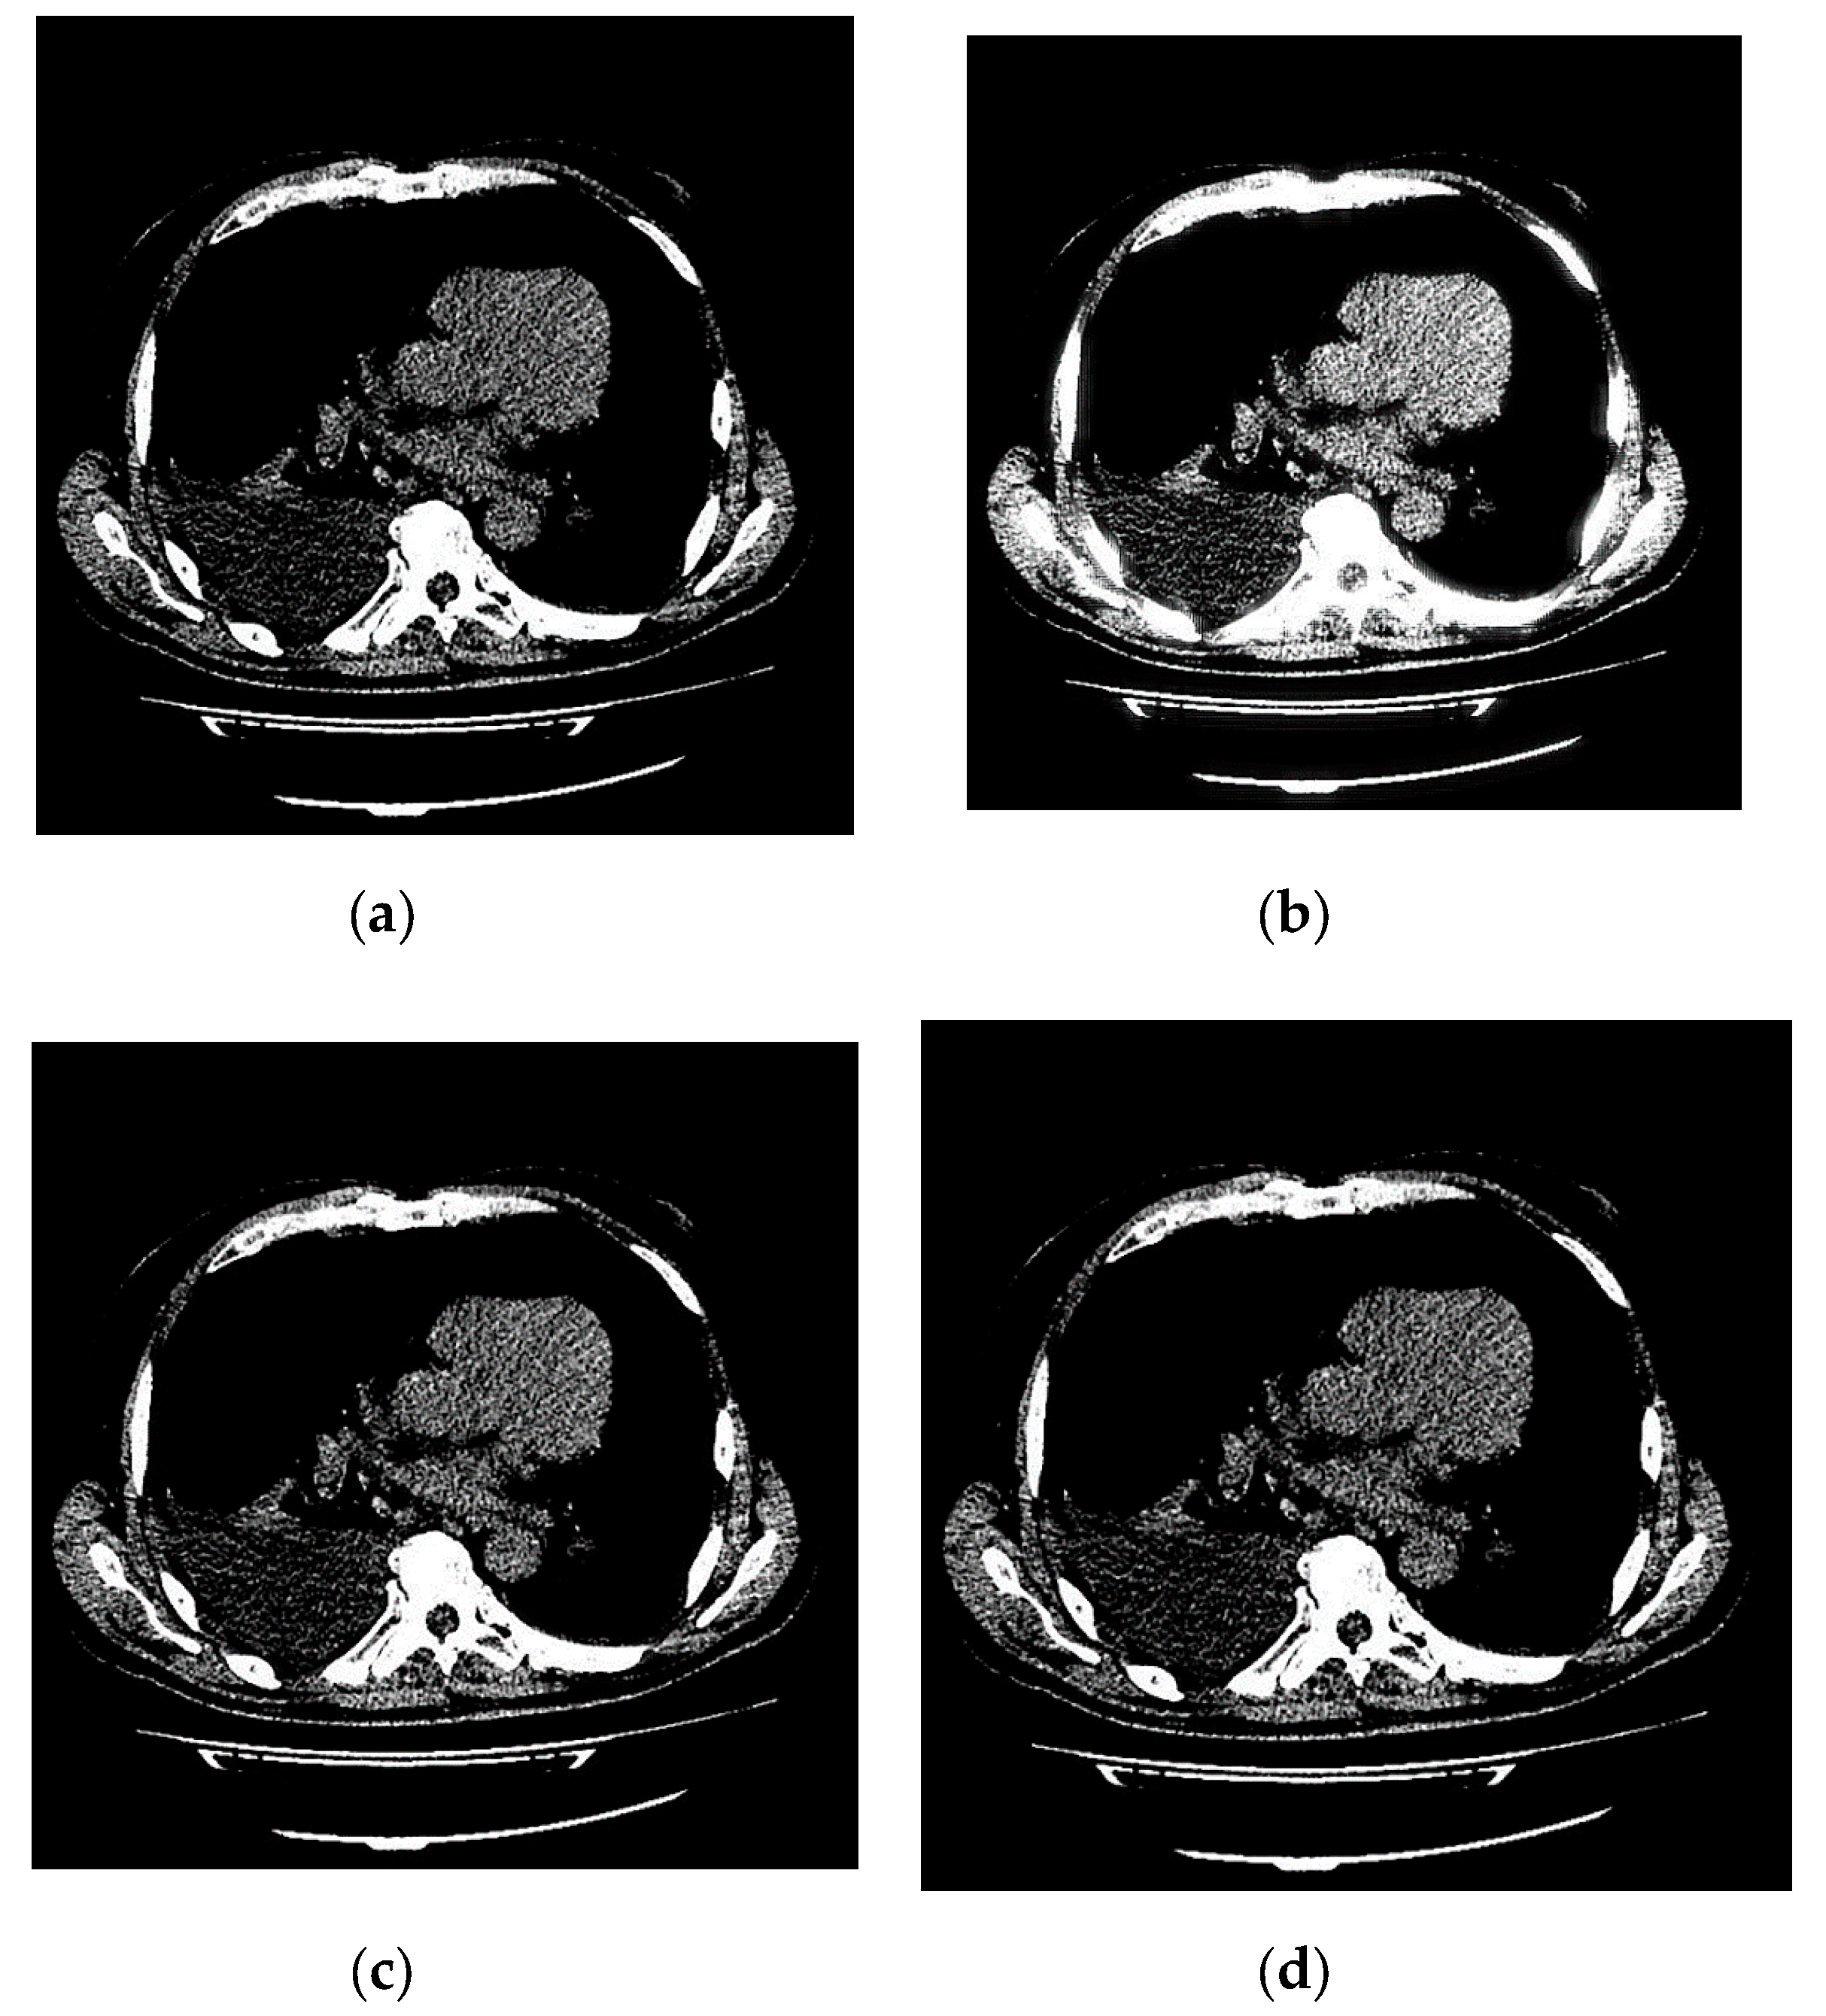

An example of 3D tomographic images “wmri”, “Trufi_COR” and “Body_1.0” DWT with wavelet d b 8 is shown in Figure 5, Figure 6 and Figure 7 respectively. Frames in Figure 6 and Figure 7 are selected to illustrate the error effect on the image processing result. Figures show a gradual improvement in the quality of processing with an increase the bit-width r : in Figure 5b, Figure 6b and Figure 7b visible distortion (Figure 5b is darkened in places, and Figure 6b and Figure 7b are lighted); in Figure 5c, Figure 6c and Figure 7c processed images are indistinguishable by eye from the original images; in Figure 5d, Figure 6d and Figure 7d processed images are identical to the corresponding originals. Experimental results are of higher quality compared with the calculation results. The values P S N R = 47.11 dB and P S N R = at r = 12 and r = 15 respectively (Figure 5) obtained after 8-bit image “wmri” DWT with wavelet d b 8 exceed the corresponding calculated values P S N R = 37.82 dB and P S N R = at r = 12 and r = 15 respectively (Table 1). The values P S N R = 64.57 dB and P S N R = at r = 12 and r = 17 respectively (Figure 6) obtained after 12-bit image “Trufi_COR” DWT with wavelet d b 8 exceed the corresponding calculated values P S N R = 36.67 dB, P S N R = 67.30 dB at r = 12 and r = 17 respectively (Table 2). Similarly, for “Body_1.0”.

Figure 5. Example of 3D tomographic 8-bit image “wmri” DWT by d b 8 wavelet: (a) original image; processed image: (b) r = 9 , P S N R = 27.62 dB; (c) r = 12 , P S N R = 47.11 dB and (d) r = 15 , P S N R = .

Applsci 10 01223 g005